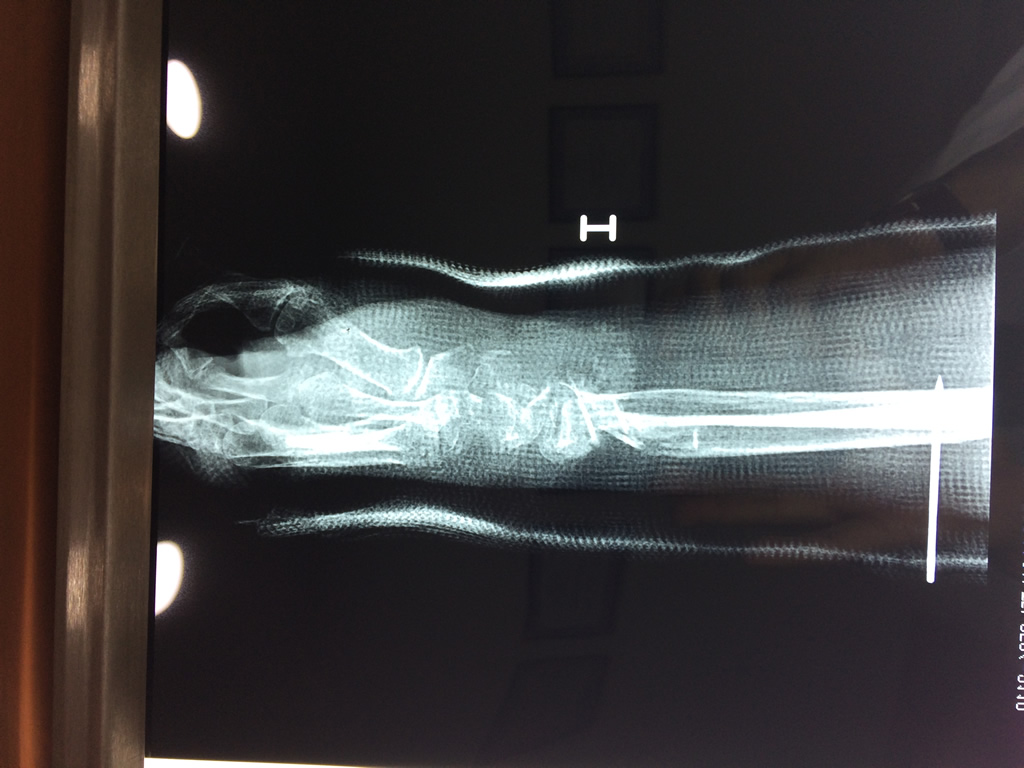

Cirugía de Fémur - Cirugías de Muñecas y Manos

Los procedimientos más comunes en cirugía de la mano son aquellos destinados a reparar traumatismos, incluyendo lesiones de tendones, nervios, vasos sanguíneos, y articulaciones; huesos fracturados; y quemaduras, cortes, y otros daños de la piel.